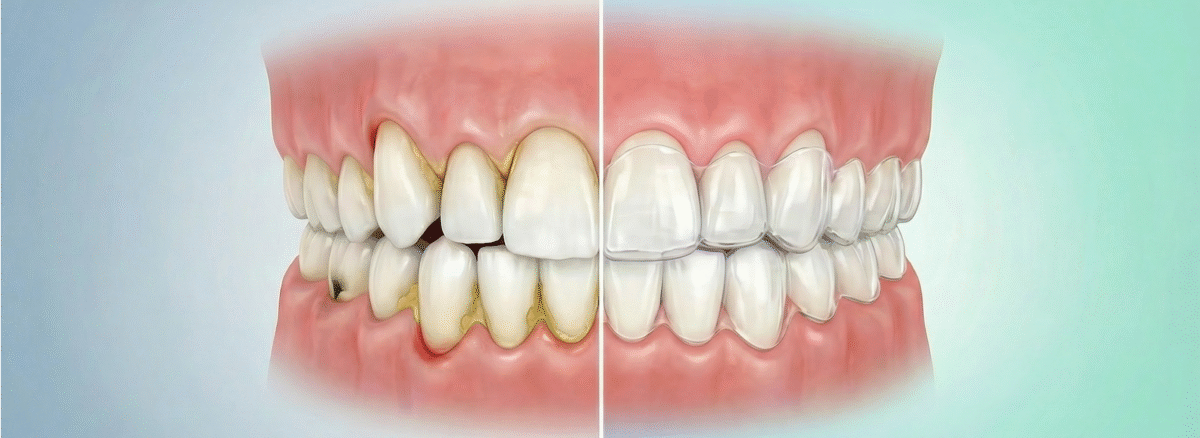

Crowded teeth create tight angles that are impossible to reach with a traditional toothbrush or even dental floss. These narrow gaps become the perfect environment for plaque and tartar buildup. Over time, this accumulation turns into tooth decay in hidden areas between the teeth—one of the hardest types of cavities to treat because it often attacks two adjacent teeth simultaneously.

Teeth that are not properly aligned place unbalanced pressure on the gum tissues and the underlying supporting bone. In cases of severe overcrowding, the tooth root may push outside its natural bony housing, leading to gum recession. This recession isn’t just a visual flaw; it is the beginning of tooth instability and extreme sensitivity.

Instead of waiting for these issues to turn into complex medical bills, Clear Aligners emerge as a smart preventive and therapeutic solution. The brilliance of this solution lies in “absolute hygiene”; since the aligners are removable, you can clean your teeth easily as they begin to straighten. This ensures your treatment journey goes hand-in-hand with protecting your teeth from cavities and gum disease.